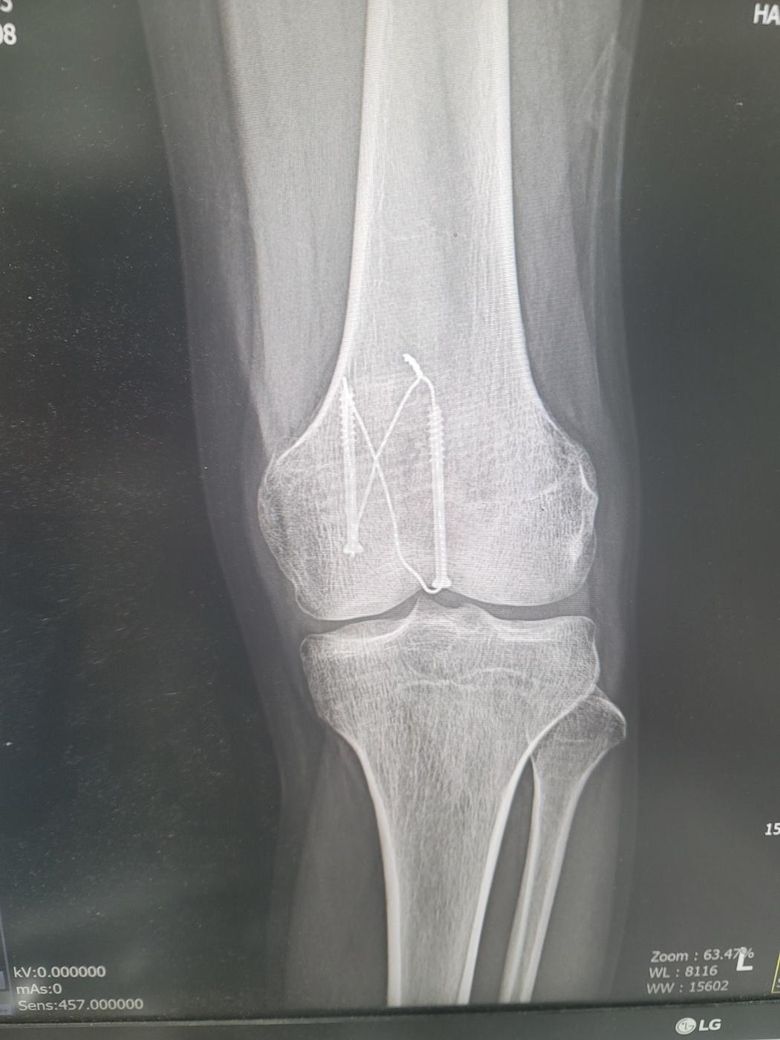

엑스레이 사진은 어제찍은 12주차 사진입니다

1. 엑스레이상 문제는 없나요?

2. 무릎에서 바깥부분부터 가로로 중간부분이 골절선처럼 움푹파여서 만져봐도 움푹파여있던데 뼈가 녹았다거나 생기다가 말수도 있는건가요? 참고로 분쇄골절입니다 ㅠㅠ

사진상으로 12주차라면 분쇄골절 회복 중인 상태로 보이고 금속 고정장치가 잘 자리 잡혀 있는 것으로 확인되어 보여요

무릎 바깥쪽 움푹 패인 부분은 골절 부위의 골융합이 아직 완전히 진행되지 않아 나타나는 정상 회복과정일 수 있습니다.

뼈가 녹았다기보다는 아직 뼈가 재형성중이거나 골편 사이가 완전히 매워지지 않은 상태로 볼 수 있습니다!

사진상 정확한 상태 파악이 어려울 수도 있지만 금속 핀 고정은 유지되어 있으며 골절 편들이 비교적 잘 맞춰져 있는 것으로 보입니다. 분쇄골절의 경우 뼈가 완전히 붙는 데 시간이 오래 걸리며 12주차 라면 아직 골소주들이 선명하게 연결되지 않은 상태로 특별한 핀 이탈이나 심한 전위가 없다면 큰 문제는 없을 것으로 생각됩니다.

무릎 중간 부분이 움푹 패여 보이는 것은 수술 후 연부조직의 위축 때문에 패여 보일 수 있으며 골절 부위의 고나절면이 함몰된 경우에도 패임이 느껴질 수 있습니다. 뼈가 녹았다기보다는 골절 치유 과정에서 흡수 재형성이 일어나거나 관절 연골의 손상 때문에 패여 보일 가능성이 있다고 생각합니다.